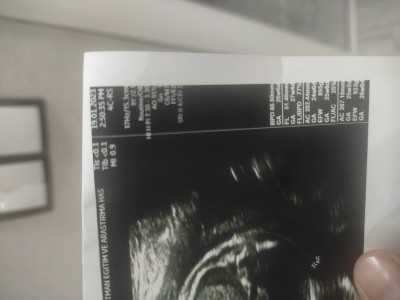

Resimli kızlar bebeğin boyu kac

Bakarmisiniz nasıl hesaplayacm

Gebelik haftası

30

FL yazan yeri 7 ile carpacaksiniz diye hatırlıyorum ben

İşte carpiyorum ama yinede anlamiyorum

İşte carpiyorum ama yinede anlamiyorum sonra cm mi ceviriyourz

Aynen cm e cevireceksiniz

FL yazan yeri 7 ile carpinca atıyorum sonuç 280 cikarsa 28 diye hesaplicaksin

36 çıktı demekki 36 cm çok teşekkür ederim

Büyğk ihtimal 42 veya 43 cm 61x7 yağınca 42.7 çıkıypr o civarlarda net gmrğnmüyor ben 61 olarak gördğm 51 de olabilir

51 yaziyor

O zamn 35 veya 36 cm